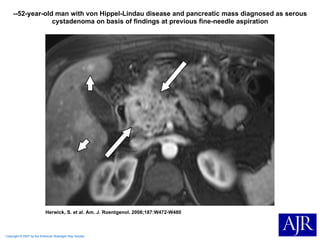

Copyright © 2007 by the American Roentgen Ray Society Herwick, S. et al. Am. J. Roentgenol. 2006;187:W472-W480 --52-year-old man with von Hippel-Lindau disease and pancreatic mass diagnosed as serous cystadenoma on basis of findings at previous fine-needle aspiration